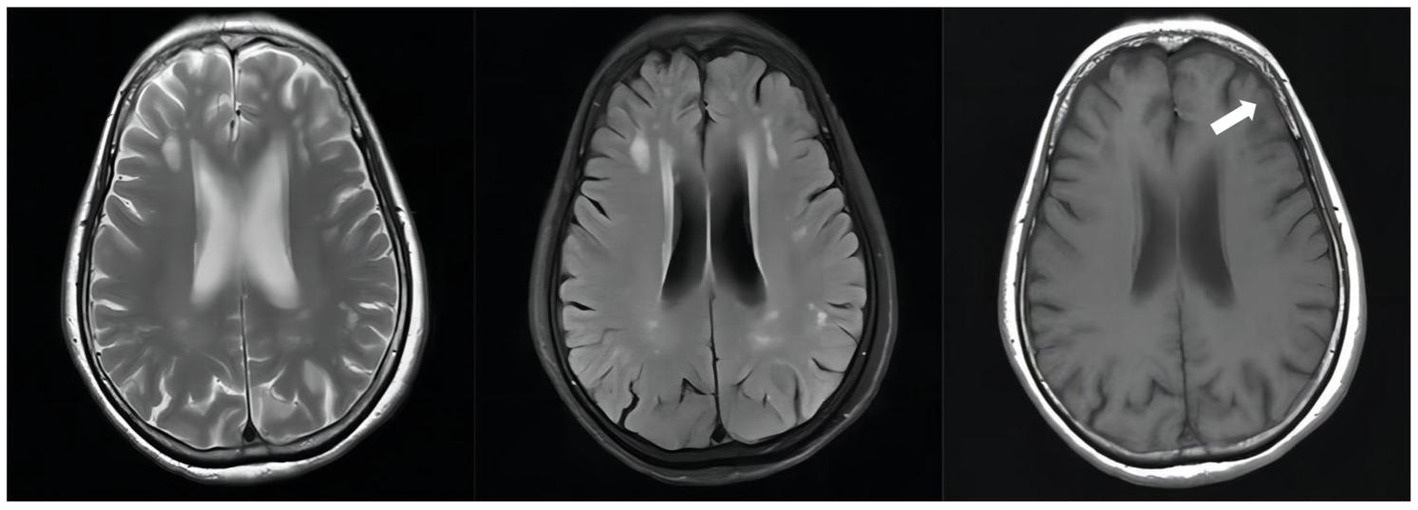

Figure 4

Unenhanced brain MRI scan on April 19, 2022(D + 74): Multiple infarcts and ischemic foci were seen bilaterally in the periventricular and frontoparietal white matter; there were abnormally enhancing lesions in the right ambient cistern, left sylvian cistern and adjacent brain parenchyma, which was considered a diagnosis of TBM, especially by referring to her medical history; also there was mild brain atrophy.

Figure 5

Follow-up unenhanced brain MRI scan on February 10, 2023(D + 371): The abnormally enhancing lesions in the right ambient cistern, left sylvian cistern, and adjacent brain parenchyma have improved.

After stopping linezolid, the adverse effects of our patient were alleviated, but CSF indicators were worsened; therefore, contezolid was used compassionately with the patient’s consent, and the improved CSF indicators were observed later (Table S1 in Supplementary material); CSF Protein also decreased from + D132 1.12 g/L↑ to + D153 0.79 g/L↑(Table S2 in Supplementary material). In the course of treatment, the patient had no obvious symptoms of mental disorders before the addition of cycloserine, and the symptoms of mental disorders gradually worsened after the addition of cycloserine, and the cycloserine was eventually discontinued, and the mental symptoms of the patient gradually improved after the discontinuation of the drug, and the use of ethambutol was eventually discontinued due to the patient’s complaint of gradual decrease in visual acuity during the course of antituberculosis treatment. With cycloserine and ethambutol discontinued due to mental symptoms, the combination regimen of isoniazid, levofloxacin, and contezolid demonstrated good anti-TB clinical efficacy and safety in this patient: the brain contrast-enhanced MRI showed continued improvement and no other adverse symptoms reported except for an intermittent numbness of both lower extremities. The successful treatment of our patient suggests that contezolid may have high blood–brain barrier permeability and possesses similar efficacy to linezolid but with significantly fewer adverse effects related to myelosuppression and peripheral neuropathy. Thus, contezolid may be a potential option to replace linezolid in future anti-TB treatment. In addition, our case is the first clinical evidence to demonstrate the efficacy and safety of long-term use of contezolid. This case has been on contezolid for eight months, and the longest reported case of contezolid use in the available published literature is a 101-year-old male patient with nosocomial vancomsycin-resistant Enterococcus faecium pneumonia who received contezolid for nearly four consecutive months, resulting in the disappearance of lesions, which may also suggest that contezolid has a good efficacy and safety profile in relevant infectious diseases (19). Our case may be helpful to provide a reference for further studies in the field of anti-TB treatment.